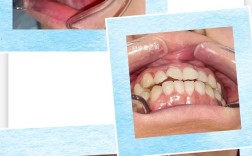

陶瓷托槽矫正

- 技术描述: 托槽由透明的生物陶瓷材料制成,颜色接近牙齿,弓丝可以是金属的(结扎在托槽上)或白色的(更美观),原理与传统金属托槽相同。